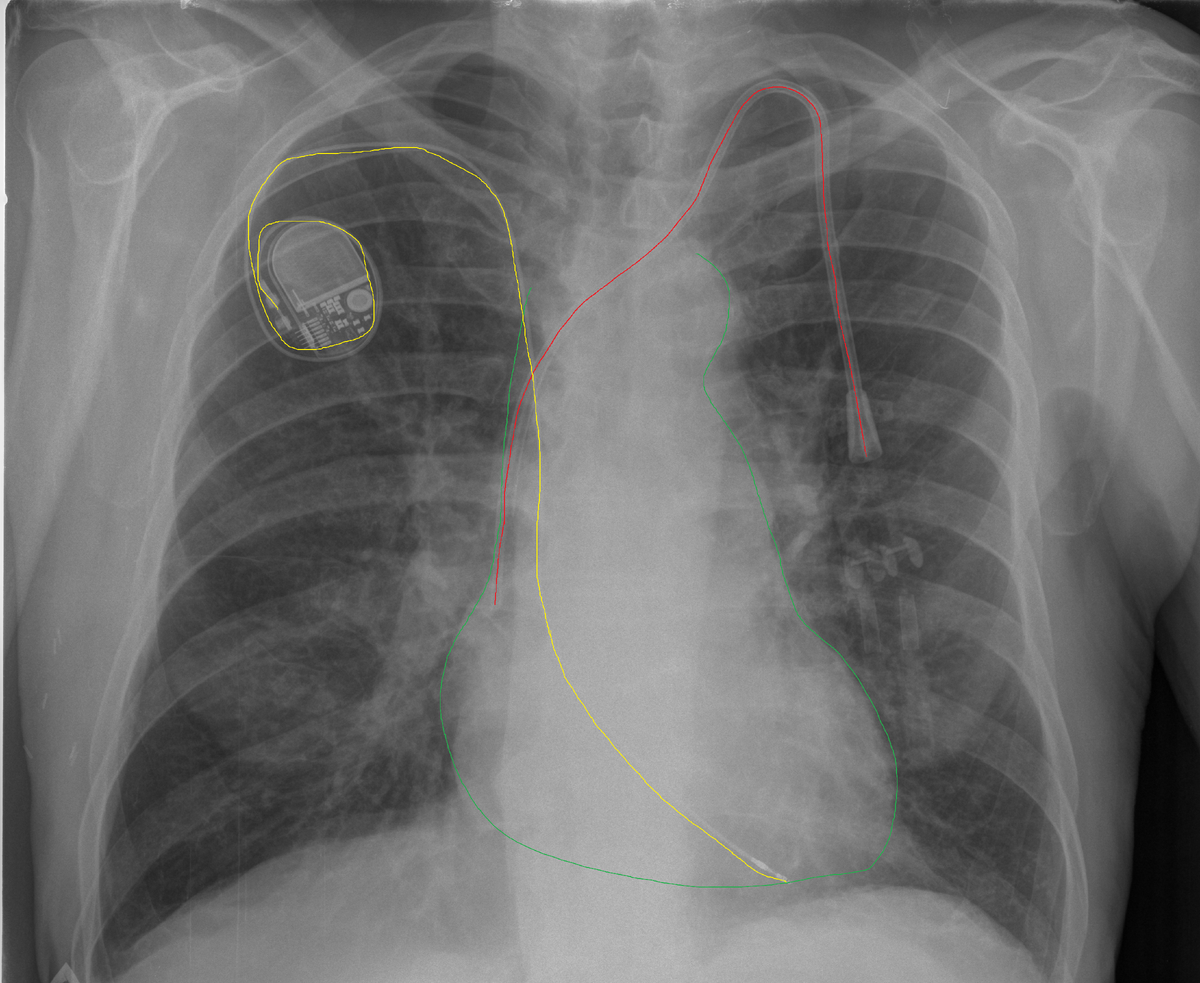

На рентгеновских снимках ЦВК визуализируются как тонкие линейные структуры, которые могут проходить от места введения (например, яремной или подключичной вены) до правого предсердия, где они должны правильно размещаться для обеспечения оптимального функционирования. Ключевыми аспектами, на которые врачи обращают внимание при интерпретации рентгенограмм, являются:

1. Положение катетера: Идеальное расположение ЦВК синдрома осуществляется вблизи передней стенки правого предсердия. Рентгенограмма позволяет врачу убедиться, что кончик катетера находится в правильной области, что минимизирует риск тромбообразования и травмирования сосудов.

2. Оценка состояния сосудов: Рентгеновские снимки также используются для визуализации вен, в которые вводился катетер. Наличие признаков разрывов, тромбообразования или других изменений может быть замечено на этих изображениях. Это позволяет врачам принимать решения о необходимости дальнейшей терапии или вмешательства.